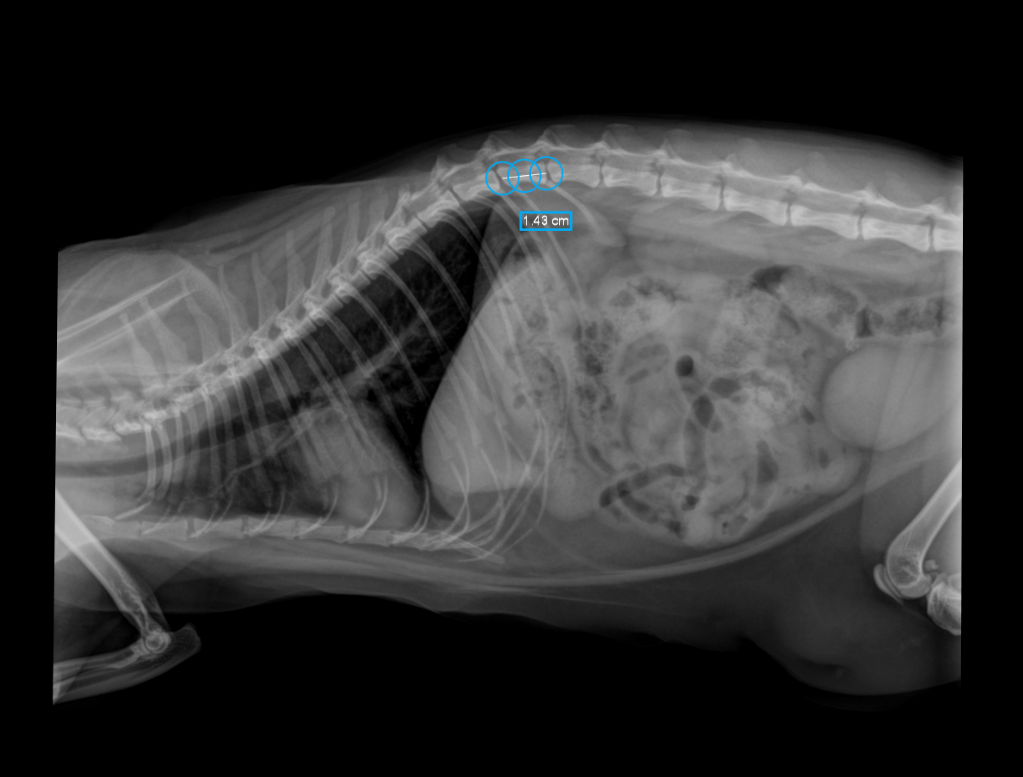

Nous sommes fières de vous annoncer que le cabinet vient de s’équiper d’un nouvel appareil de radiographie numérique.

Très utile pour évaluer la fonction locomotrice, digestive ou encore respiratoire, cet examen permet d’investiguer de multiples troubles et d’affiner de nombreux diagnostics.